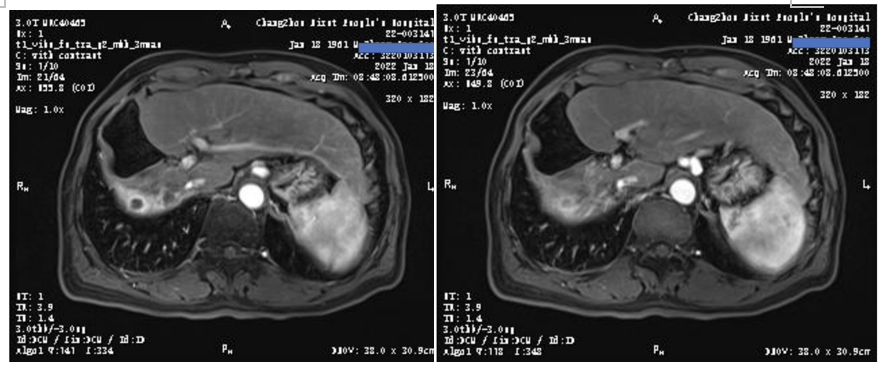

2022年1月18日复查MR提示,肝左叶基本看不到明显的活性病灶,较2020年11月MR明显好转(图10)。

图10.2022年1月18日复查MR